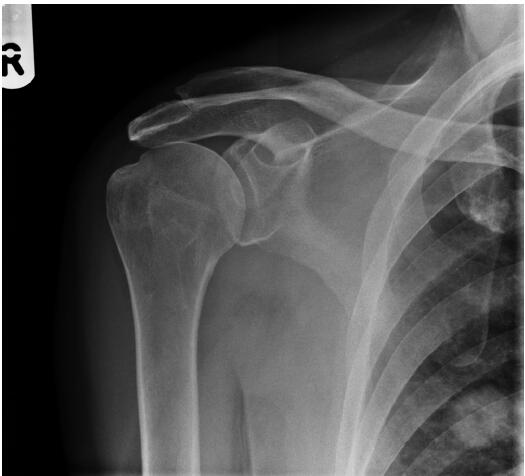

患者,男性,62歲,跌倒后,肩膀越來越疼。全科醫(yī)生要求該患者進(jìn)行放射檢查(圖1)。

圖1右肩前位X光平片

僅根據(jù)影像學(xué)檢查,需要的下一步檢查是什么?